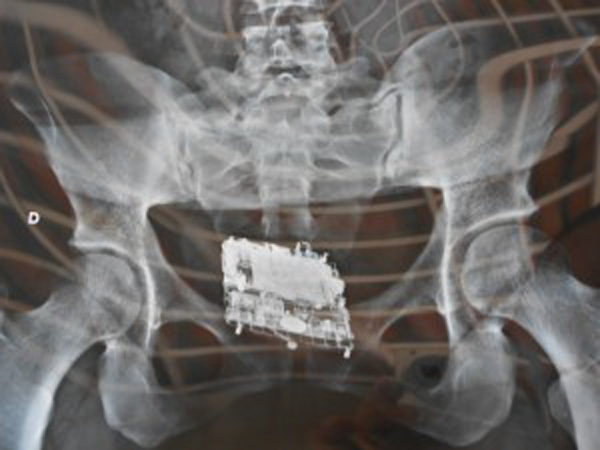

Celular no intestino da mulher | Foto: Reprodução/Internet

De acordo com o diretor, a agente penitenciária da Cadeia de Quixadá percebeu um escorrimento na região genital de uma auxiliar doméstica. Ela pretendia visitar o marido. Para evitar algum constrangimento desnecessário, já que ela negava a existência de qualquer objeto introduzido no seu corpo, a alternativa encontrada foi conduzi-la até o Hospital Municipal Eudásio Barroso, onde foi feito o Raio X. Quando a chapa foi revelada a equipe da Cadeia Pública ficou surpresa. Havia um aparelho celular no ânus dela. O objeto mede 5cm de largura por 6,5cm de comprimento. Estava num preservativo.